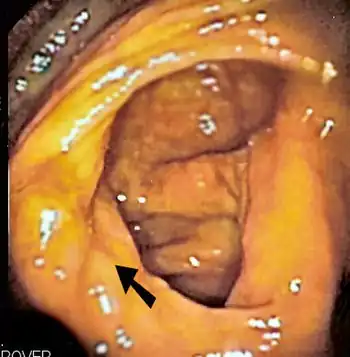

The ileocecal valve prevents reflux of bacteria from the colon into the small bowel. Resection of the valve can lead to bacterial overgrowth.

The diagnosis of SIBO is made by several techniques, with the gold standard[3] being an aspirate from the jejunum that grows more than 105 bacteria per millilitre. Risk factors for the development of SIBO include dysmotility; anatomical disturbances in the bowel, including fistulae, diverticula and blind loops created after surgery, and resection of the ileo-cecal valve; gastroenteritis-induced alterations to the small intestine; and the use of certain medications, including proton pump inhibitors.

Finally, abnormal connections between the bacteria-rich colon and the small bowel can increase the bacterial load in the small bowel. Patients with Crohn's disease or other diseases of the ileum may require surgery that removes the ileocecal valve connecting the small and large bowel; this leads to an increased reflux of bacteria into the small bowel. After bariatric surgery for obesity, connections between the stomach and the ileum can be formed, which may increase bacterial load in the small bowel.[21]